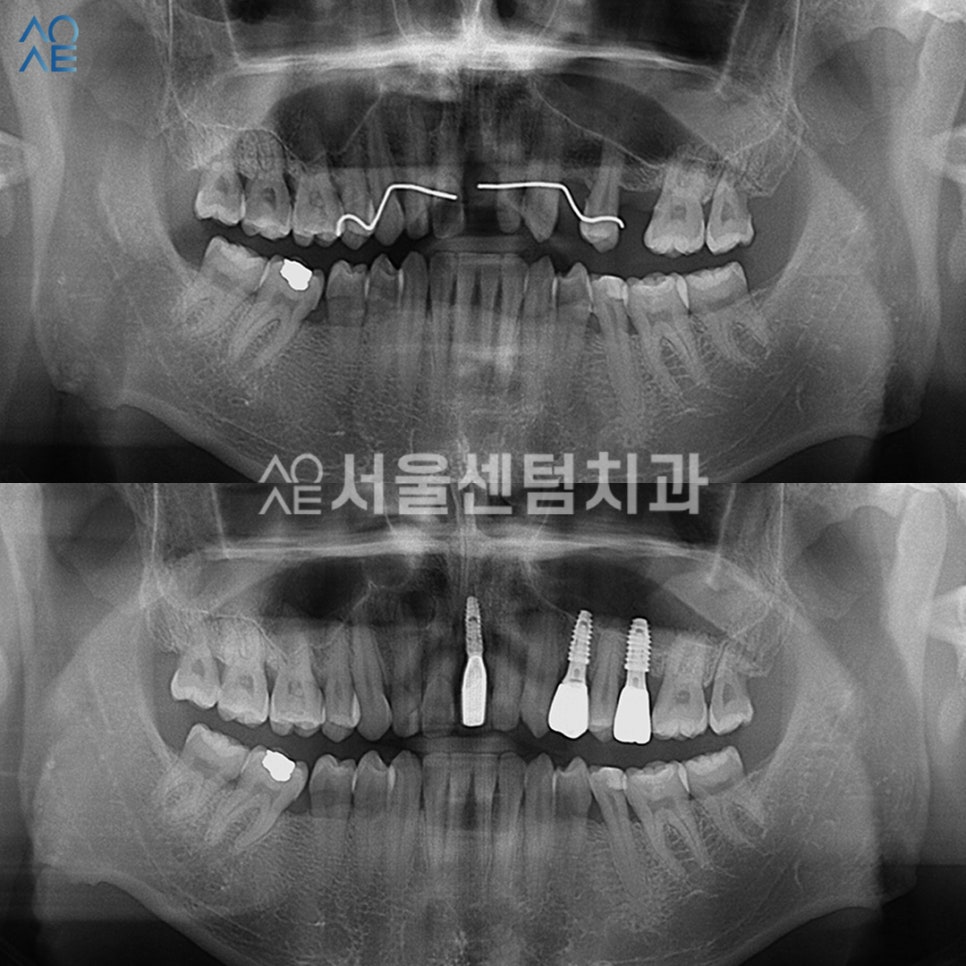

앞니 임플란트 치료 시작

진단과 상담을 마친 후

환자분께서 바로 치료하시길 희망하셔서

당일 식립 수술을 진행했습니다.

이러한 경우엔 시작이 빠르기 때문에

전체적인 치료 기간이 단축될 수 있었습니다.

총 3개를 식립하였고

잇몸 상태가 좋지 않아 뼈이식도 함께 진행했습니다.

또한 왼쪽 윗부분에는 식립을 위한

공간을 만들기 위해 상악동 거상술도

진행해야 했습니다.

치료 경과

임플란트기간 그리고 경과에 궁금하신 분들을 위해

조금 자세히 적어보겠습니다.

일단 이 분의 경우엔 뼈이식도 진행하였고

잇몸 상태가 좋지 않았기 때문에

충분히 기다리는 시간이 필요했습니다.

또한 2차 수술도 필요한 케이스로

2차수술 직전에 CT를 촬영하여

잇몸뼈가 잘 형성되었는지 확인 후

진행을 했습니다.

개인에 따라서 경과를 지켜보는 기간이 다르며

이 분은 4개월 후에 보철물을 제작하기로 했습니다.

앞니임플란트 완료

각 부위별로 잇몸치료를 진행 후

어금니쪽 보철물을 먼저 수복하였습니다.

앞니는 제일 마지막에 제작하였고요.

기간 차이는 있었지만

전부 성공적으로 마무리되었습니다.

이 분은 특히 어려운 수술인

상악동거상술도 함께 진행하였고

앞니여서 심미성도 신경써야했습니다.

성공적인 앞니임플란트 결과

기간은 총 4개월 조금 넘게 걸렸습니다.